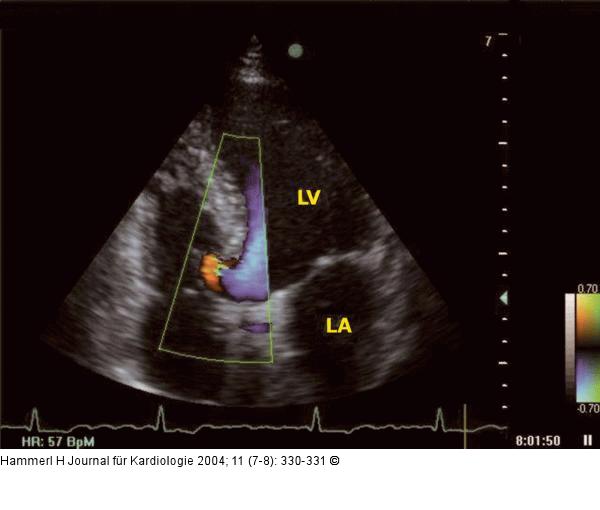

Abbildung 3: Interventrikuläres Septum - Aneurysma Apikaler Vierkammerblick - Farbdopplerstudie: Flow-Verhältnisse im Bereich des Aneurysma ohne interventrikulären Shunt; LA = linker Vorhof; LV = linker Ventrikel |

Apikaler Vierkammerblick - Farbdopplerstudie: Flow-Verhältnisse im Bereich des Aneurysma ohne interventrikulären Shunt; LA = linker Vorhof; LV = linker Ventrikel |